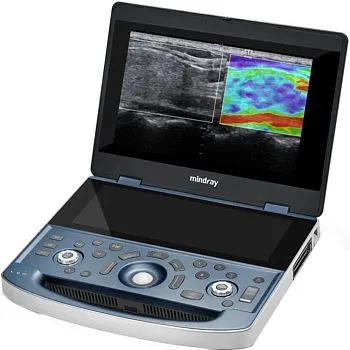

УЗИ аппарат Mindray MX7 портативный

УЗИ аппарат Mindray MX7 портативный

Mindray MX7 — высокотехнологичный портативный УЗИ аппарат, предлагающий впечатляющее качество изображения и широкий функционал. Благодаря своей компактности и мобильности, Mindray MX7 идеально подходит для работы в условиях ограниченного пространства или для выездных обследований. Портативный Mindray MX7 обладает передовыми технологиями, позволяющими получать четкие и детальные изображения в реальном времени. Благодаря различным режимам сканирования и широкому выбору датчиков, этот сканер может применяться в различных областях медицины, от акушерства и гинекологии до кардиологии и онкологии.

Приобретение УЗИ аппарата Mindray MX7 — надежное решение для клиник и врачей, которые ценят качество и точность диагностики. Надежность, мобильность и высокая производительность делают Mindray MX7 отличным выбором для специалистов, которым важны результаты и удобство работы. Вы можете заказать или купить со склада в наличии портативный УЗИ аппарат Mindray MX7 по выгодной цене, от надежного официального дистрибьютора Миндрей МСТ, с бесплатной доставкой в любой город.

Компактный дизайн и совершенная эргономика

- Вес 3 кг и толщина 44 мм (в сложенном состоянии) - сверхлегкая и тонкая портативная ультразвуковая система

- 15,6-дюймовый IPS монитор

- 12,3-дюймовый сенсорный экран обеспечивает пользователю интуитивно понятное управление

- Высокая мобильность и гибкость

Высокая автономность

Сверхдолгое время автономной работы - до 8 часов. U-bank, усовершенствованный аккумулятор, беспроводная зарядка: длительная работа и максимальное удобство.Расширенные возможности диагностики